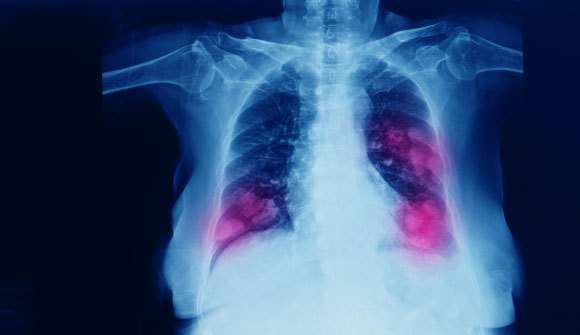

כך נראה הסרטן הקטלני בעולם, בישראל הוא גורם המוות המוביל מסרטן. סרטן ריאות דו-צדדי בצילום רנטגן | Yok_onepiece, Shutterstock